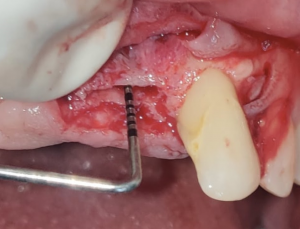

- Ridge Split surgeries for dental implants

- Guided Bone Regenerative procedures using membrane and bone grafts